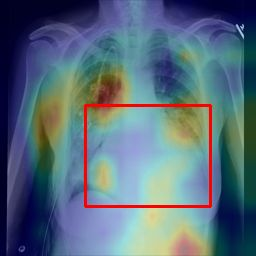

Deployments of artificial intelligence in medical diagnostics mandate not just accuracy and efficacy but also trust, emphasizing the need for explainability in machine decisions. The recent trend in automated medical image diagnostics leans towards the deployment of Transformer-based architectures, credited to their impressive capabilities. Since the self-attention feature of transformers contributes towards identifying crucial regions during the classification process, they enhance the trustability of the methods. However, the complex intricacies of these attention mechanisms may fall short of effectively pinpointing the regions of interest directly influencing AI decisions. Our research endeavors to innovate a unique attention block that underscores the correlation between 'regions' rather than 'pixels'. To address this challenge, we introduce an innovative system grounded in prototype learning, featuring an advanced self-attention mechanism that goes beyond conventional ad-hoc visual explanation techniques by offering comprehensible visual insights. A combined quantitative and qualitative methodological approach was used to demonstrate the effectiveness of the proposed method on the large-scale NIH chest X-ray dataset. Experimental results showed that our proposed method offers a promising direction for explainability, which can lead to the development of more trustable systems, which can facilitate easier and rapid adoption of such technology into routine clinics. The code is available at www.github.com/NUBagcilab/r2r_proto.